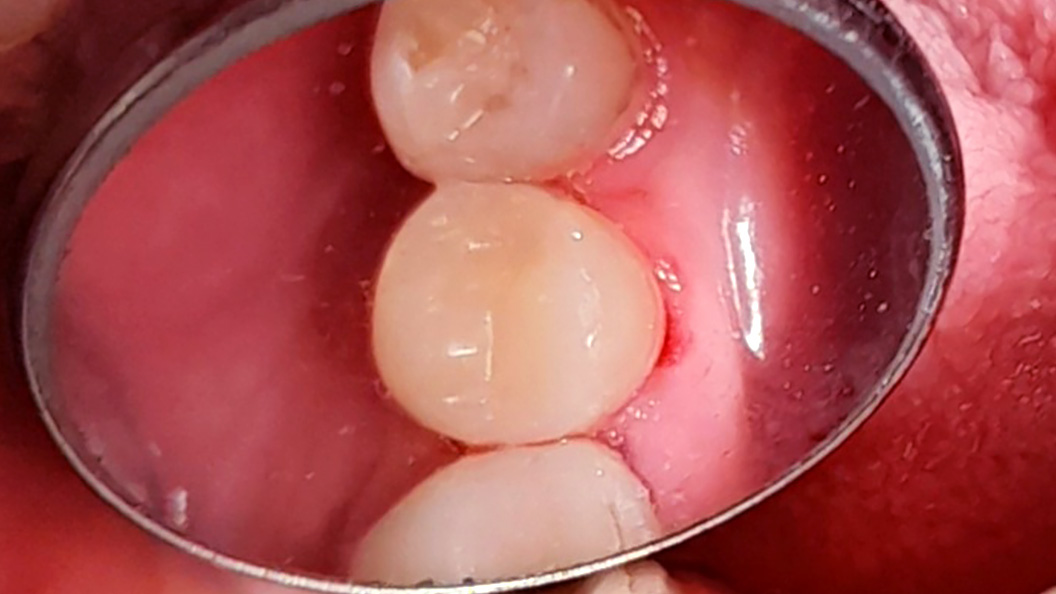

До и после лечения

В «Стоматологию Комфорта» обратился пациент с жалобами на выпадение пломбы из 45 зуба и кратковременные боли от приёма холодных продуктов. Врач-стоматолог-терапевт Похилько Н. Г. в ходе осмотра выявила кариозную полость на мезиально-окклюзионно-дистальной поверхностях 45 зуба. Зондирование было болезненно, перкуссия — безболезненна. Был поставлен диагноз: хронический глубокий кариес 45 зуба. Врач пришёл к выводу о лечении с последующей установкой пломбы из светоотверждаемого композита Estelite.

Композитный материал Estelite с рентгеноконтрастными свойствами качественно и быстро полимеризуется под воздействием светового излучения. Вещество незаметно в месте пломбирования благодаря высоким эстетическим показателям. Это очень прочный материал с отличными физическими и механическими характеристиками, на 82% состоящий из композитного и кремниево-циркониевого наполнителя.